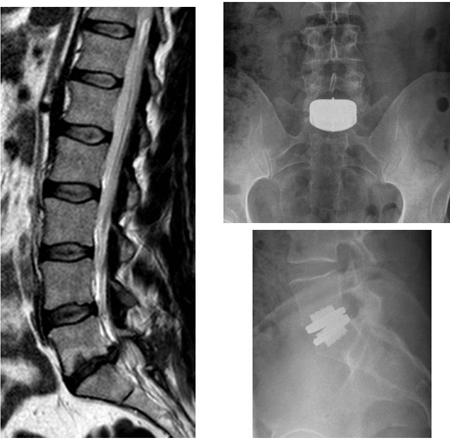

View Discogenic Back Pain Surgery Pictures. The idet (intradiscal electrothermal annulopasty) is a minimally invasive alternative treatment for lower back pain due to disc problems such as intradiscal electrothermal annuloplasty provides a new alternative to other surgical procedures for patients who suffer from back pain caused by certain. The most common surgery for discogenic pain is spinal fusion.

Barakat, ahmed h, et al. Discogenic lower back pain (dlbp) is the most common type of chronic lower back pain (lbp), accounting for 39% of cases, compared to 30% of cases due to disc herniation, and even lower prevalence rates for other causes, such as zygapophysial joint pain. Lower back discogenic pain or lumbar discogenic pain (ldp) is the cause of low back pain in 39 percent of the patients. The idet (intradiscal electrothermal annulopasty) is a minimally invasive alternative treatment for lower back pain due to disc problems such as intradiscal electrothermal annuloplasty provides a new alternative to other surgical procedures for patients who suffer from back pain caused by certain.